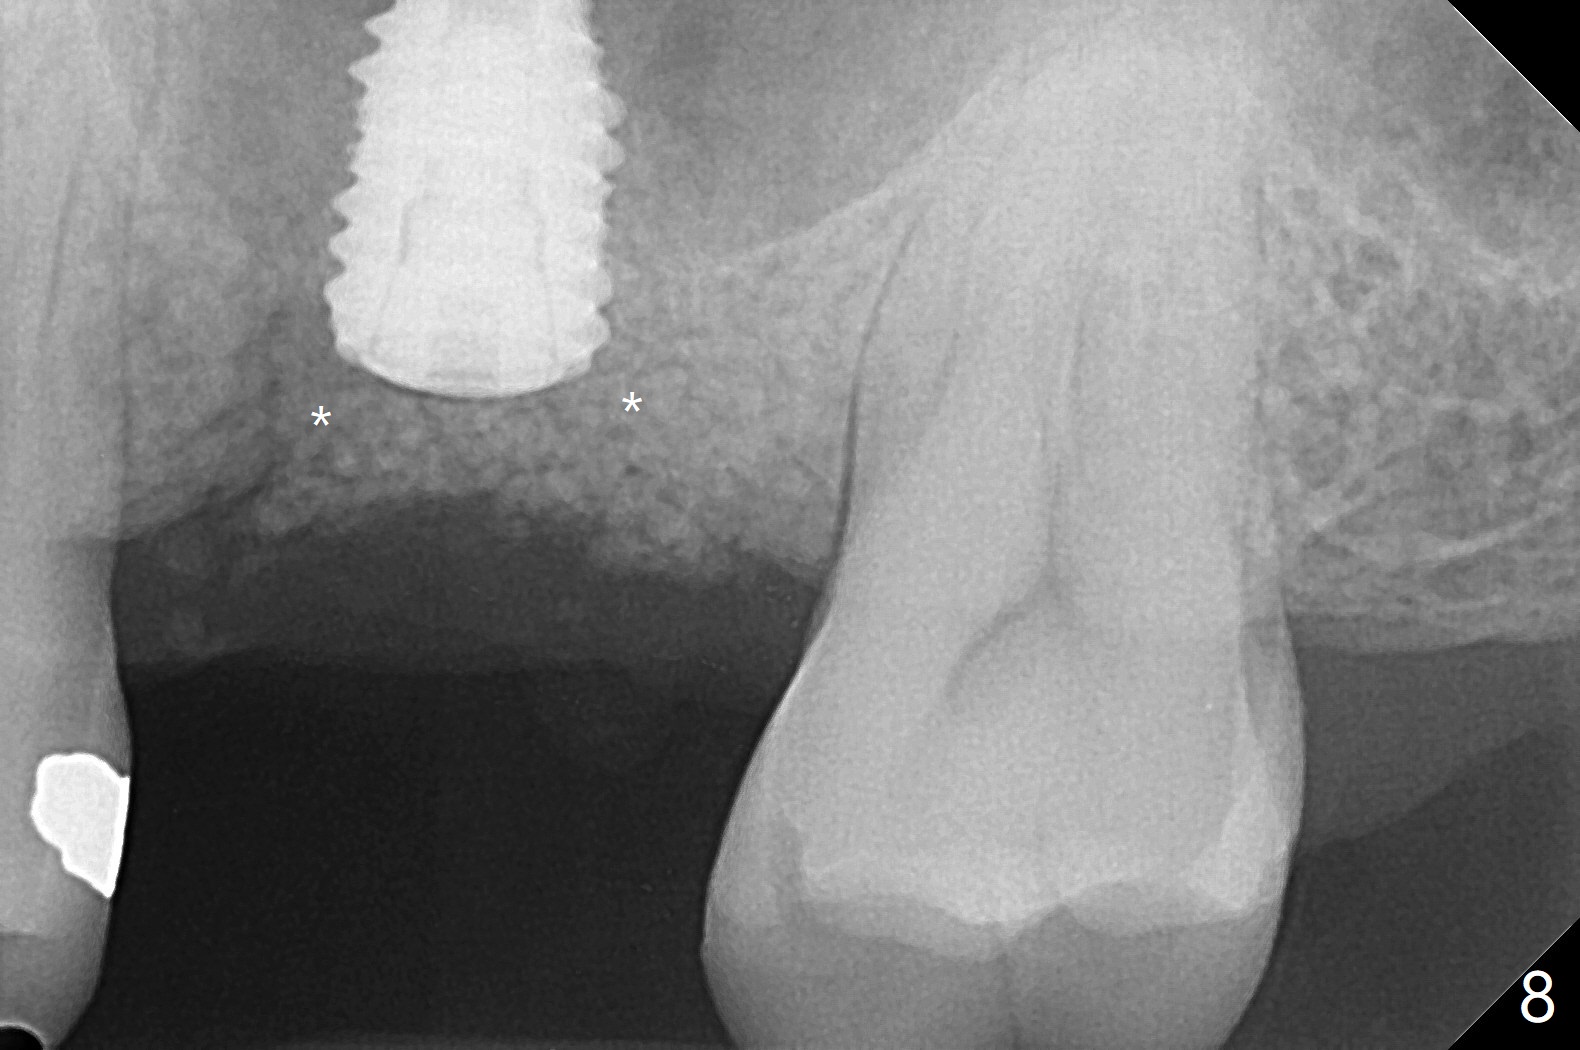

After using 4.5x5.3 mm and 3.5x7.3 mm drill at #14 with guide, the sinus floor is not perforated. When a 4.5x11 mm dummy implant is placed to the 2nd line (12 mm offset), the sinus membrane is perforated (Fig.1). A piece of PRF membrane and sticky bone are pushed into the sinus in an attempt for repair. A shorter implant is placed (5x7.3 (instead of 8.5) mm, Fig.2,3,5, as compared to Fig.3) to reduce postop sinus infection. In fact incision reveals palatal bony concavity. When the implant is placed, there is mild palatal thread exposure. With incision instead of tissue punch, it is easy to place bone graft over the small defect (Fig.3 *). The wound dehisces and heals 2 weeks postop (Fig.6). There is bone loss 6.5 months postop (Fig.7 *), corresponding to palatal thread exposure. After decortication and periosteal underscoring, cortical allograft mixed with ~.25 cc GEM21S is placed (Fig.8 *).